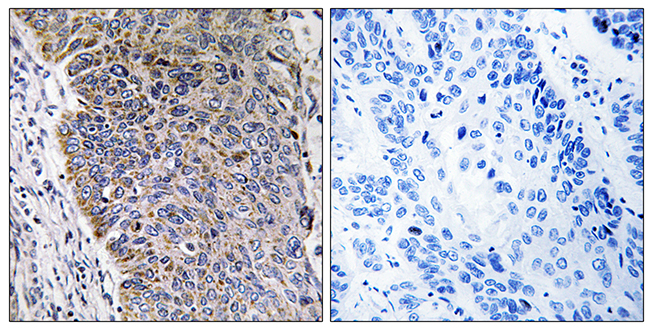

Anti-MED21 AntibodyA98863

ApplicationsELISA, ImmunoHistoChemistry

ReactivityHuman, Mouse

- SizePrice